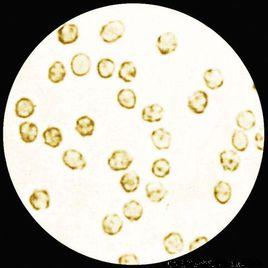

正常人尿中出現的少量紅細胞以及無腎小管間質損害的腎小球疾病患者尿中的紅細胞都是畸形紅細胞。這是由於正常腎小管記憶體在滲透梯度,尤其是髓襻外支粗段小管液低滲濃度使紅細胞發生裂變變形。腎小球性血尿中紅細胞的畸形還可能是在紅細胞通過腎小球基膜時受到擠壓,造成破損所致。

如果是腎盞、腎盂、輸尿管、膀胱或尿道出血,即非腎小球性血尿,在等張或高張尿中,其紅細胞的形態,大小絕大多數是正常的,僅小部分為畸形紅細胞。某些腎小球疾病可出現混合性或均一性血尿,這是由於出現了腎小管間質病變,腎小管內不能形成正常的滲透梯度,由這部位腎單位來的紅細胞就不會變形。當存在較為廣泛的腎小管間質損害時,紅細胞形態即可成為均一性的。

鑒於上述原因,套用紅細胞位相檢查來鑑別血尿來源時,必須同時考慮腎小球及腎小管間質病變情況。在無腎活檢的條件下,可結合滲透分子清除率(CoSM)綜合判斷,因為CoSM反映了腎小管間質病變的程度。一般認為,正常人尿中有紅細胞者約4%,其中紅細胞數(0.5~5.0)×1012/ml〔即500一5000/毫升〕,多為正常紅細胞。如尿中發現畸形紅細胞(其大小,形態呈多形性,血紅蛋白含量異常)占75%以上,且紅細胞數≥8000/毫升者,可診斷為腎小球性血尿。